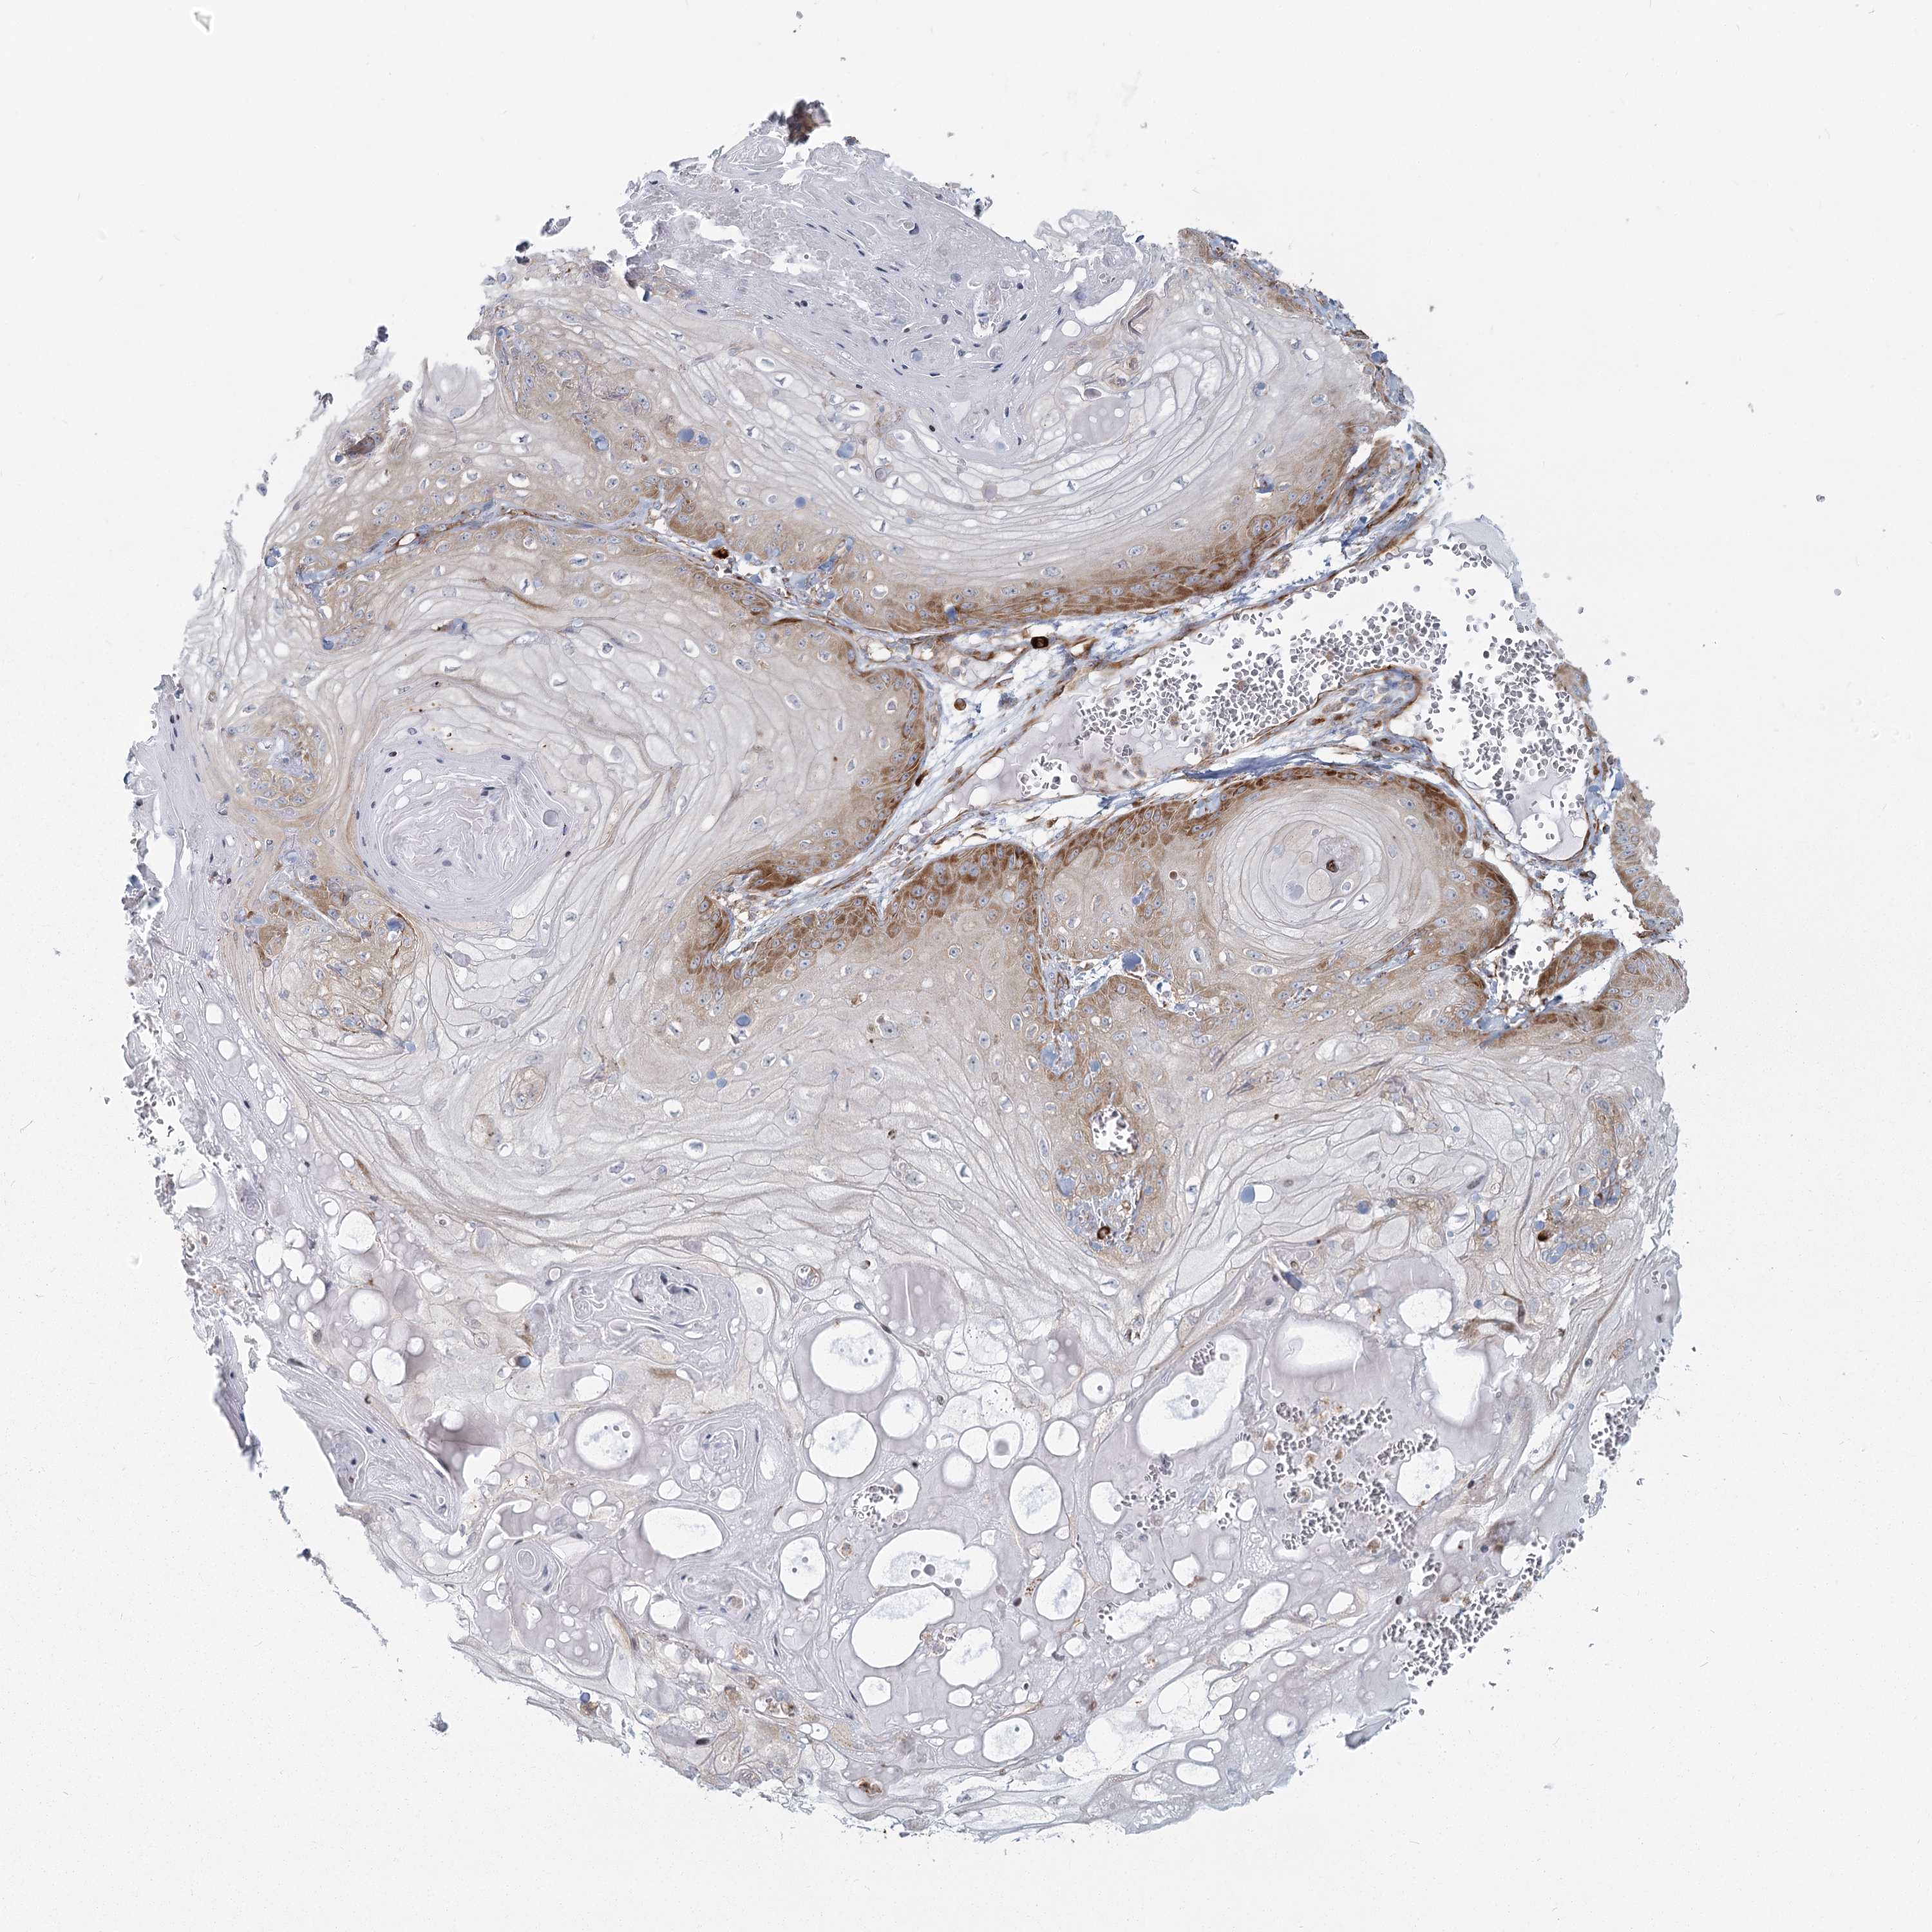

Basal cell and squamous cell cancer

SKIN CANCER - Protein expressioni

A mouse-over function shows sample information and annotation data. Click on an image to view it in a full screen mode. Samples can be filtered based on level of antibody staining by selecting one or several of the following categories: high, medium, low and not detected. The assay and annotation is described here.

Antibody stainingi

Antibody staining in the annotated cell types in the current human tissue is reported as not detected, low, medium, or high, based on conventional immunohistochemistry profiling in selected tissues. This score is based on the combination of the staining intensity and fraction of stained cells.

Each image is clickable and will lead to virtual microscopy that enables deeper exploration of all samples and also displays staining intensity scores, fraction scores and subcellular localization as well as patient and tissue information for each sample.

Antibody HPA035941

Staining

High

Medium

Low

Not detected

Intensity

Strong

Moderate

Weak

Negative

Quantity

>75%

75%-25%

<25%

None

Location

Nuclear

Cytoplasmic/membranous

Cytoplasmic/membranous,nuclear

Basal cell carcinoma